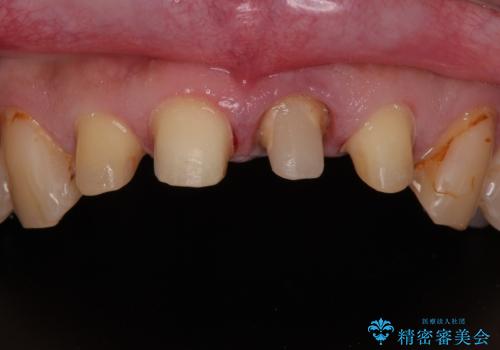

- 前歯の見た目を良くしたいとのことで来院された患者様です。今までに保険のプラスチック(コンポジットレジン)で虫歯の治療をしており経年的な劣化により着色が目立つようになっていました。また歯と歯の隣り合っているところに段差もあり虫歯になっていたり、詰め物も外れていたため前歯4本のオールセラミッククラウンによる治療を行うこととなりました。

拡大鏡視野下で保険のプラスチック(コンポジットレジン)、虫歯、左上1の被せものを除去し、オールセラミッククラウンに適した形にしました。